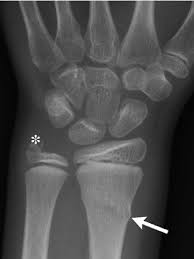

Carpal Bones Wikipedia from upload.wikimedia.org Drag the slider over the image to reveal or remove the highlighted bones of the radiograph labels: Only the proximal carpal bones are labeled and the distal ulna and radius. Pa radiograph of the wrist. Articulates with ulnar carpal bone. Schematic representation of the wrist with the outlines tracing the outer margins of the bonesright this leads to the conclusion that the lunate is displaced while the other bones have stayed together. They are usually divided into two rows: (a) distal phalanx 1st digit, (b) interphalangeal joint, (c) proximal phalanx 1st digit. Start studying carpal bones labeling anatomy.

Carpi), are the eight bones of the wrist that form the articulation of the forearm with the hand. The term carpus is derived from the latin carpus and the greek καρπός (karpós). Triangular appearance of lunate on frontal projection. Study the carpal bones as pieces of a jigsaw puzzleleft: Capitate and all other carpal bones lie posterior to lunate on lateral radiograph. The carpus is a composite joint composed of all the articulations to which the seven carpal bones contribute. Occurs when the lunate maintains normal position with respect to the distal radius while all other carpal bones are dislocated posteriorly. The carpal bones are the eight small bones that make up the wrist (or carpus) that connects the hand to the forearm. An easy and convenient way to make label is to generate some ideas first. The carpal bones are the eight bones of the wrist that form the articulation of the forearm with the hand. If an abnormal alignment of the carpal bones is depicted during imaging of the. Articulates with ulnar carpal bone. Dynamic instability is present if the carpal bones appear normal in standard radiographs taken at rest, but abnormal movement is identified in clinical examination, radiographic stress views, or cineradiography.

Lunate Bone Wikipedia from upload.wikimedia.org The term carpus is derived from the latin carpus and the greek καρπός (karpós). Pa radiograph of the wrist. {label gallery} get some ideas to make labels for bottles, jars, packages, products, boxes or classroom activities for free. Avascularity of the scaphoid, as assessed on preoperative radiographs, was characterized by loss of trabecular structure, collapse of subchondral bone, and formation of bone cysts. Log in through your library. The primary etiologic factor is trauma courtesy of dr. They can be divided in two rows: View carpal bones research papers on academia.edu for free.

Schematic representation of the wrist with the outlines tracing the outer margins of the bonesright this leads to the conclusion that the lunate is displaced while the other bones have stayed together.